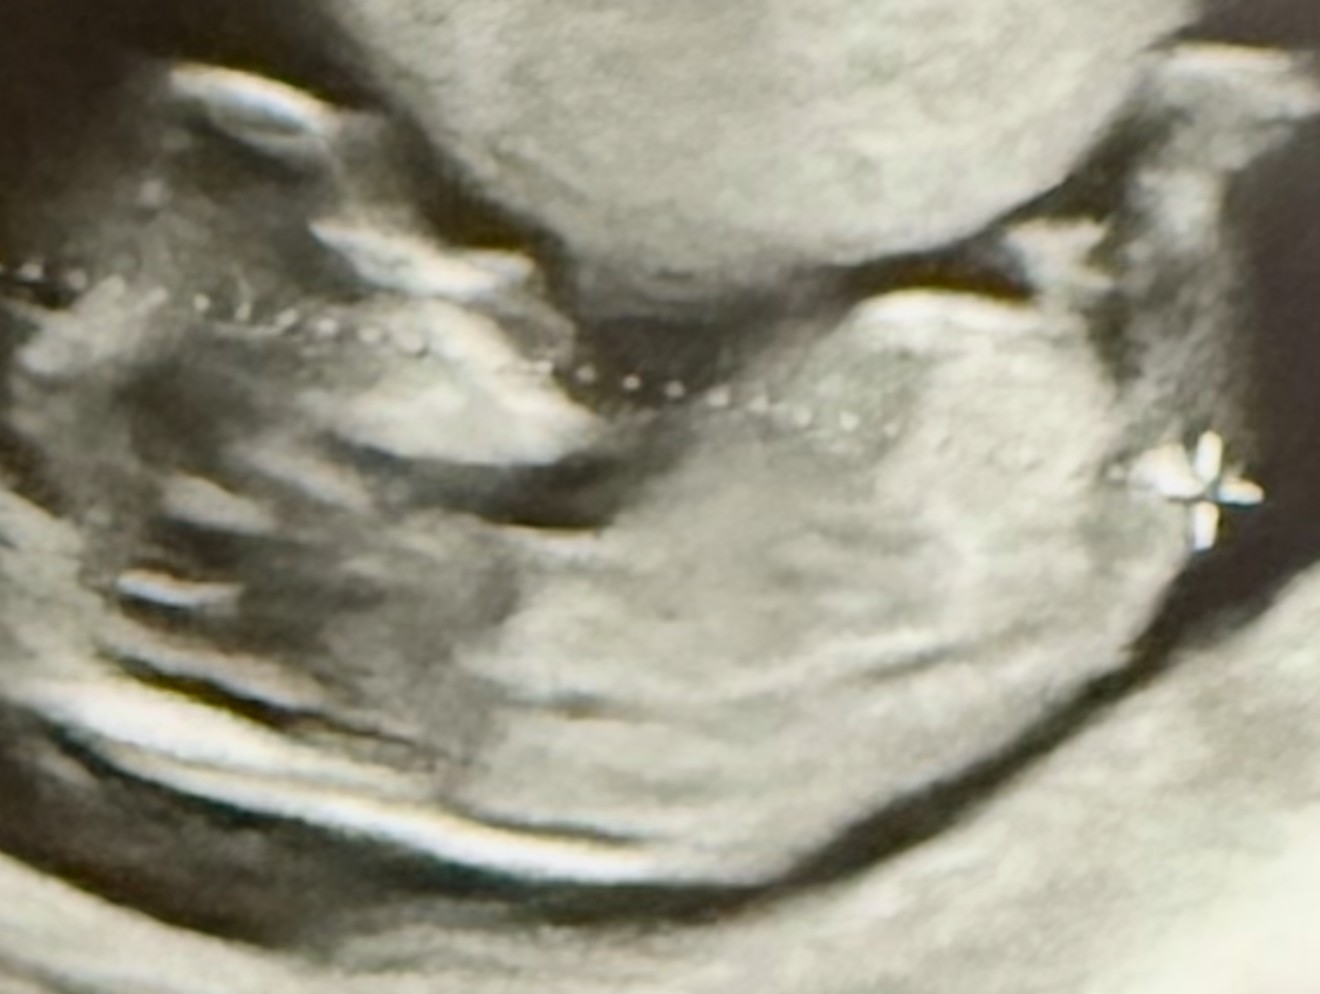

Witam serdecznie czy któraś z was z tego USG potrafi wywnioskować płeć?

Mi się wydaje że coś tam widzę między nogami tam gdzie zaznaczyłam kółeczkiem.

Jeżeli to zdjęcie z 1 prenatalnych, to na tym etapie ciąży nie ma jeszcze nic konkretnego między nogami, jest wyrostek płciowy. Mają go obie płcie.

Jeżeli lekarz nie zaryzykował zgadywanki to zostaje poczekać do prenatalnych w 2 trymestrze.